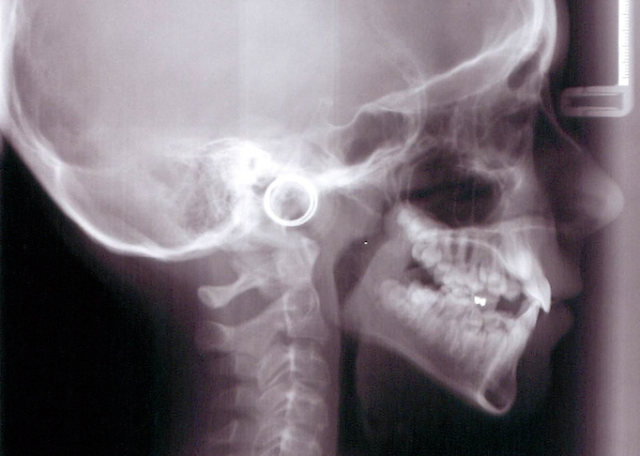

The challenge often lies in controlling the vertical dimension particularly in cases of excess vertical facial height. Vertical control is often linked with controlling the eruption of second molars. I have often heard the question asked why some orthodontists do not bond the second molars. In some cases the decision could be related to vertical control. As the most distal contact and hinge point, any increase in the eruption of the second molar can result in a discouraging anterior bite opening and increased overjet as the mandible rotates down and backward. A heavy wire extended to the second molar can easily accomplish this undesirable result in a vertical growth pattern. (Fig. 1 and 2)